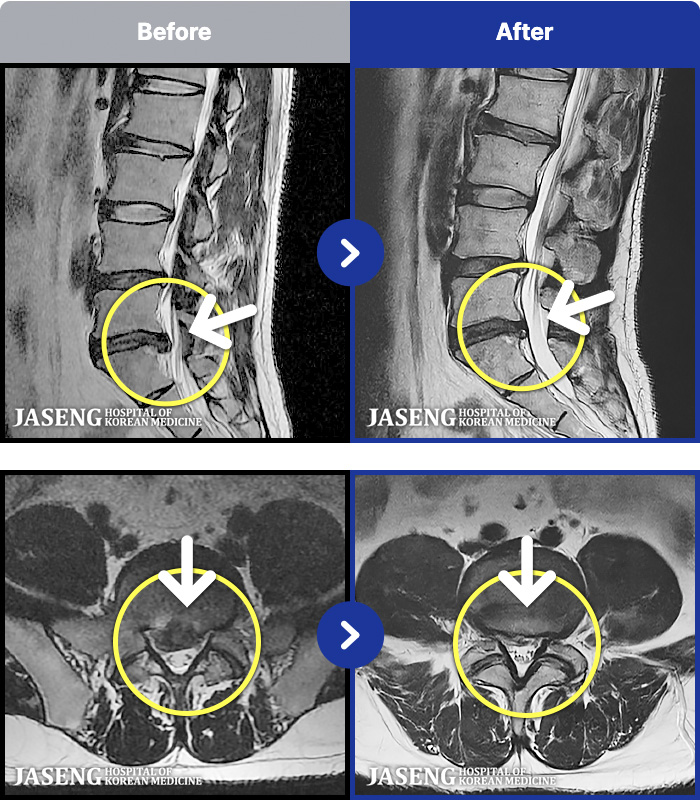

MRI ġ

54 MRI ũ ʸ Ȯϼ.